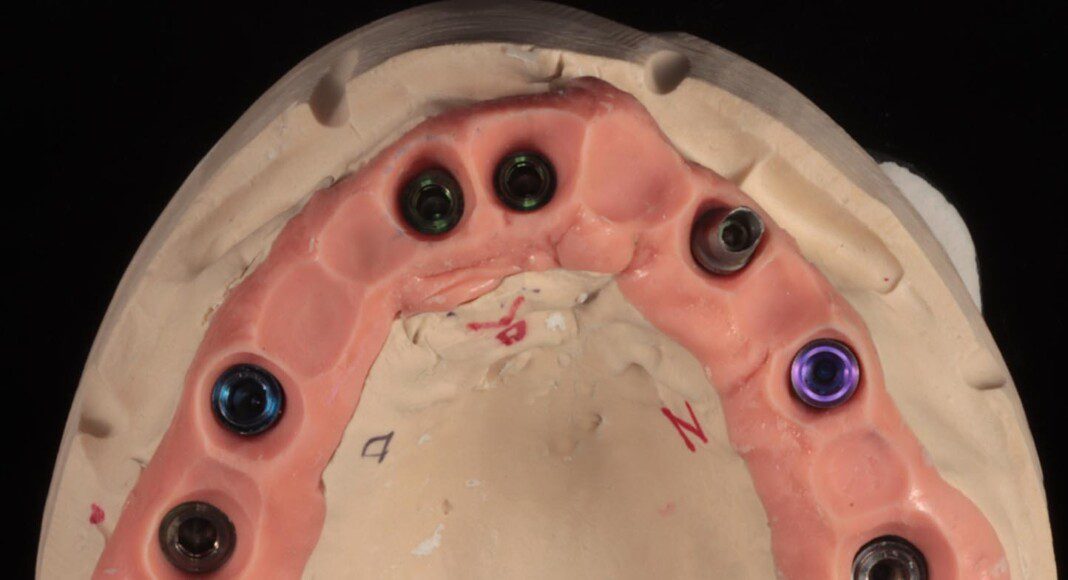

Zirconia bridge cemented to the titanium cylinders (tissue view) + one cemented unit on one old implant. The angle of this implant was too far forward. By cementing this one, we can still use it for retention and stability. Note the convex nature of the tissue interface for easy cleaning.